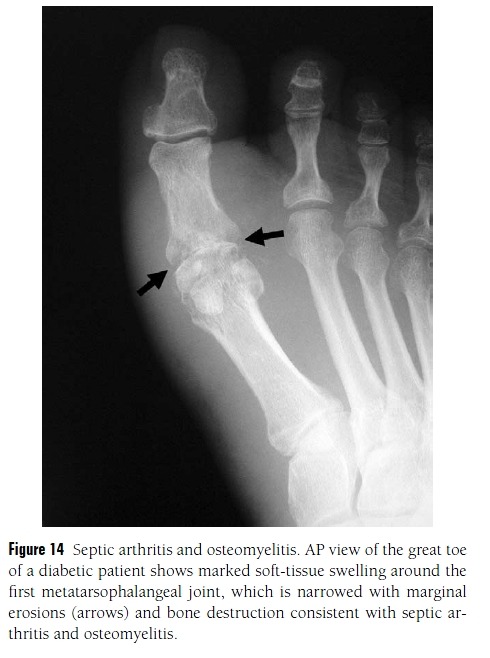

Figure 12 Osteoarthritis.

(A) Osteoarthritis of the first metatarsophalangeal joint is common; a prominent dorsal osteophyte may form

(arrow) called a “hallux rigidus spur.” Like impingement syndromes at the ankle, this condition is associated with pain and limited range of motion at the joint.

(B) Ankle joint osteoarthritis with anterior impingement. Lateral view of the ankle shows narrowing of the

ankle joint (arrowheads) and subchondral sclerosis representing osteoarthritis. Anterior spurs (arrows) can cause pain and limited dorsiflexion, called “anterior impingement.”